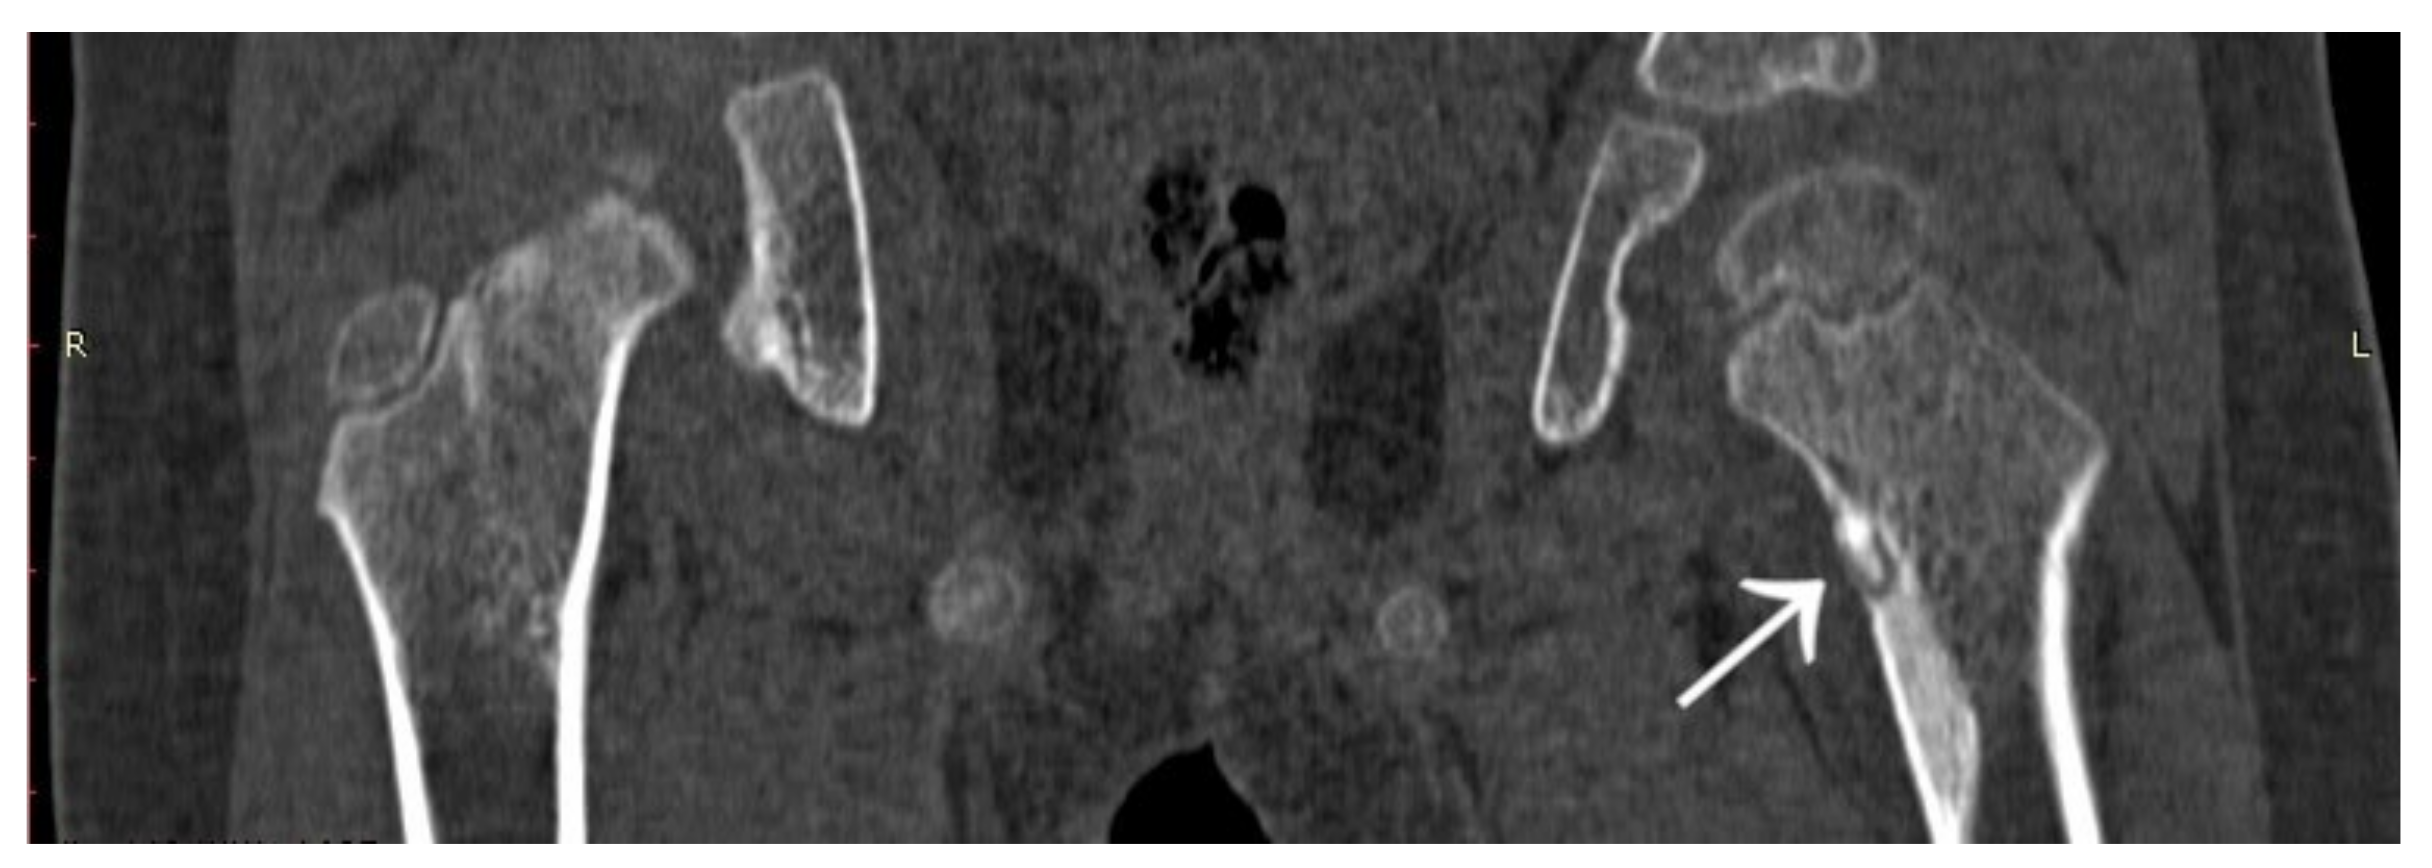

Figure 8.

MRI scan of the hip joints; subtle changes (arrow) in the right femoral neck made suspicion of fatigue fracture, no focus of OO revealed initially.

Figure 9.

X-ray view of internal stabilisation with three cannulated screws of the right femoral neck.

Figure 10.

CT scan of the hip joints showing a focus of OO in the right femoral neck.

A 31-year-old male patient with post-exercise and night pain was seen at an orthopaedic outpatient clinic for diagnosis. The patient underwent a pelvic X-ray and an MRI scan of the right hip joint. The MRI description suggested a suspected fatigue fracture of the right femoral neck (Figure 8). The patient was qualified for surgery. Under general anaesthesia, internal stabilisation was made with three cannulated screws (Figure 9). During the following six months after surgery, the pain did not resolve. During further diagnosis, the patient had a CT scan of the hip joints. The examination revealed a focus of OO of 10 × 9 × 6 mm in the right femoral neck (Figure 10). The patient underwent thermoablation with intraoperative 3D navigation without complications (Figure 11). The VAS score of pain on the day of surgery was 7. Night and postoperative pain resolved completely. The VAS score on examination 3 months after surgery was 0. Cannulated screws were not removed.